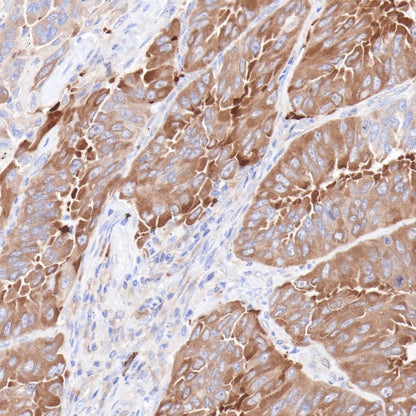

IHC shows positive staining in paraffin-embedded human ovarian cancer.

Anti-Hsp90 beta antibody was used at 1/2000 dilution, followed by a Goat Anti-Rabbit IgG H&L (HRP) ready to use. Counterstained with hematoxylin.

Heat mediated antigen retrieval with Tris/EDTA buffer pH9.0 was performed before commencing with IHC staining protocol.